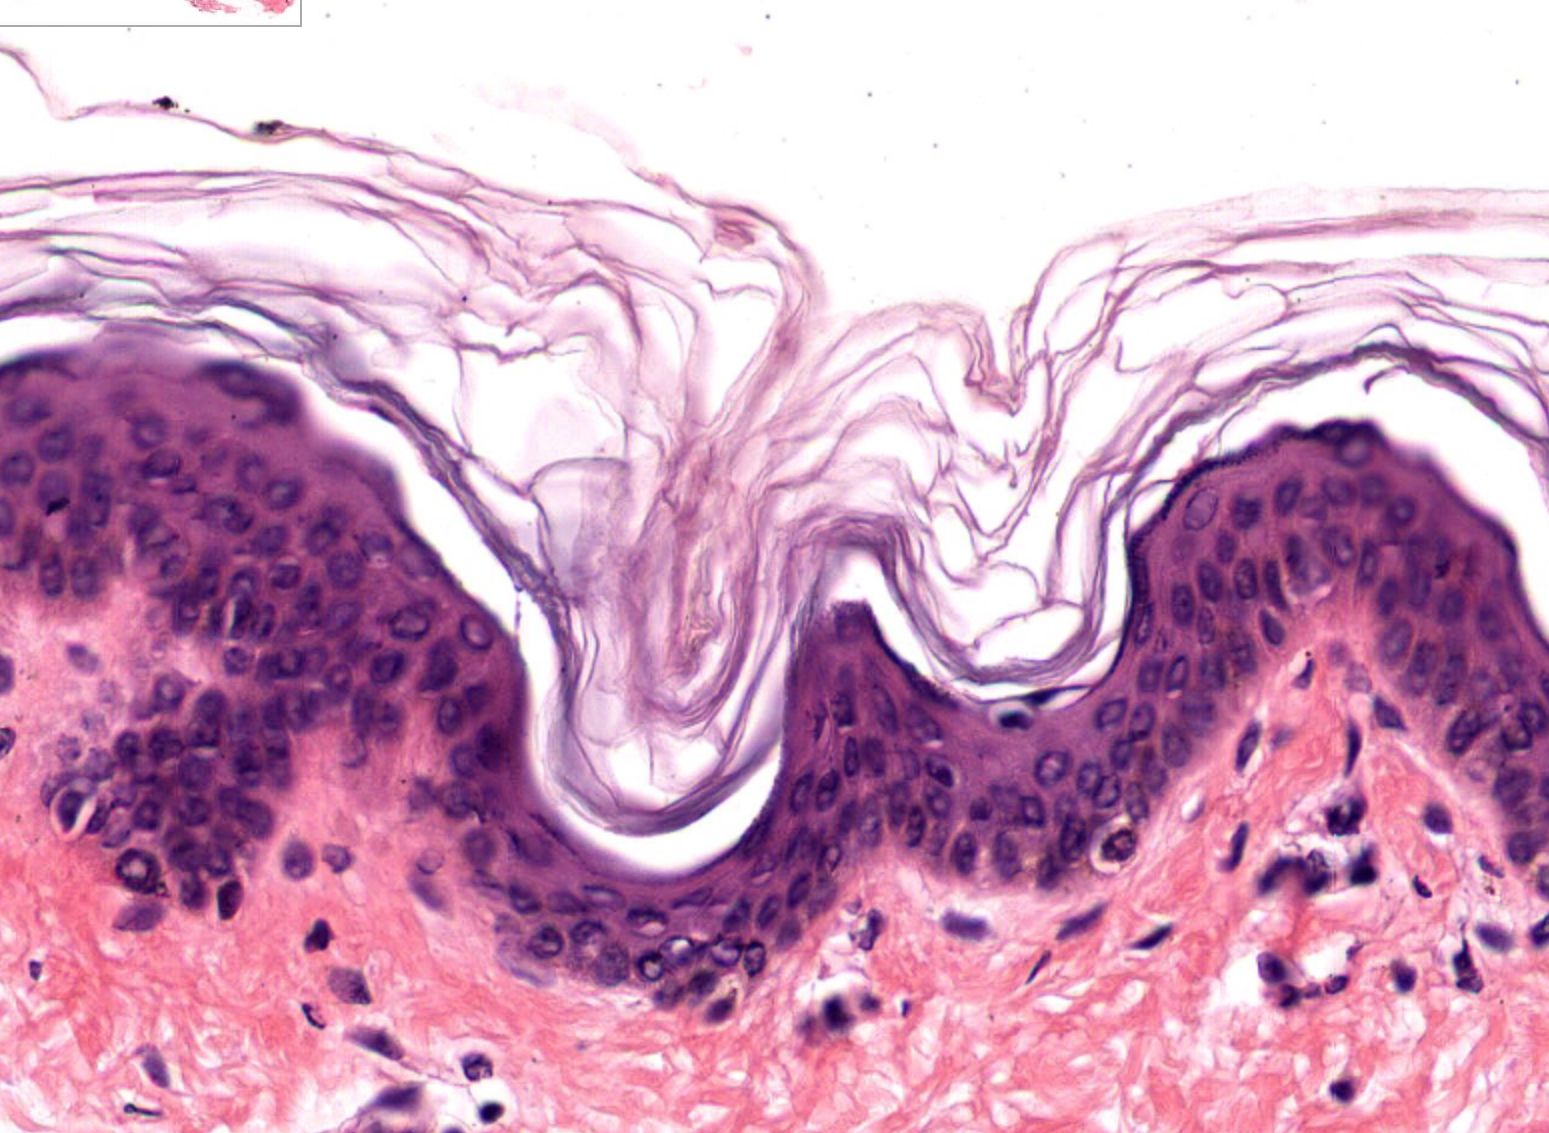

term image

Tissue: Dense Irregular Connective Tissue

Location: Dermis

Function:

• strength and elasticity